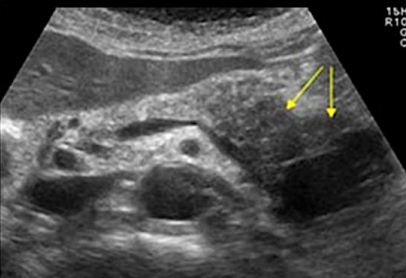

Acute pancreatitis with stone obstructing the pancreatic duct

Describe this image

Diagnosis?

Gallbladder with wall thickening and a stone obstructing the common bile duct causing dilatation (posterior shadowing). Results in pancreatitis

Dx: gallstones/pancreatitis